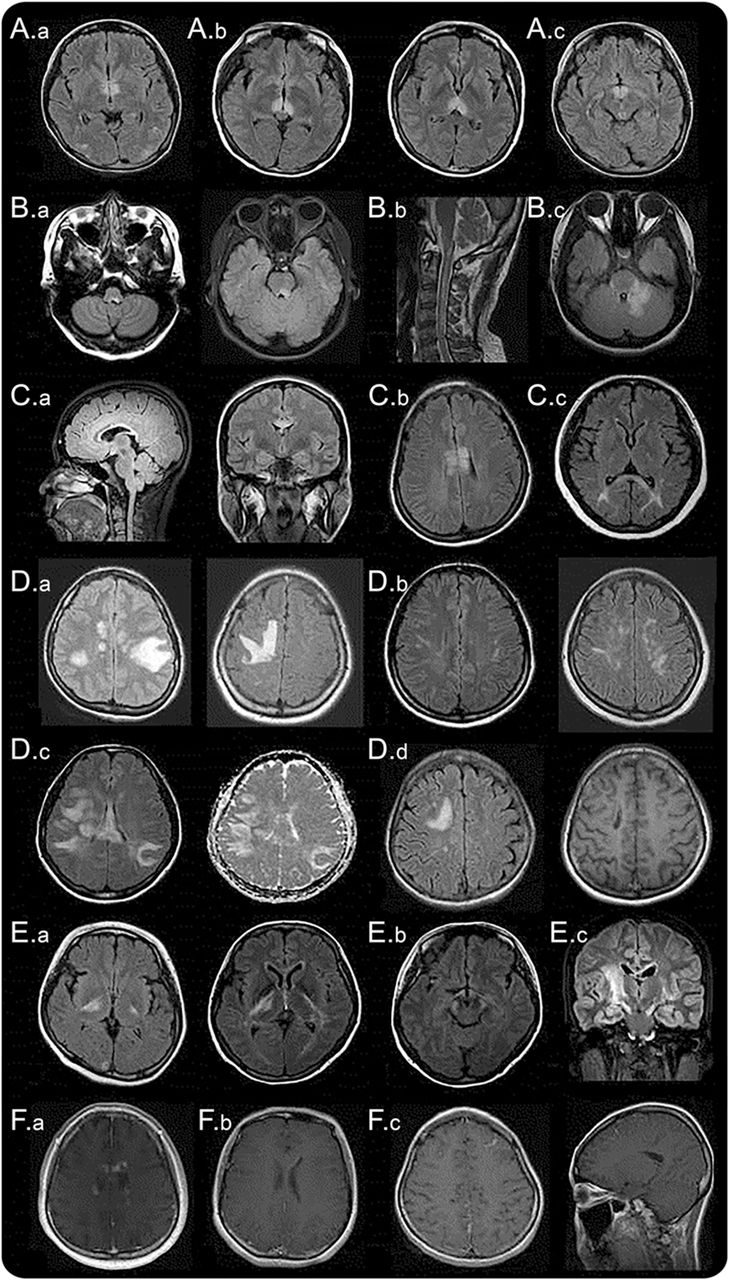

间脑的病变周围(一)第三脑室和脑导水管,(A.b),包括丘脑、下丘脑、中脑的前边缘(交流)。(本科)背脑干损伤邻近第四脑室,(反方向)线性髓病变与颈脊髓损伤,相邻(公元前)水肿和大量的背侧脑干病变涉及小脑脚。(一个)立即胼胝体病变侧脑室,室管膜衬后,(C.b)“大理石模式”胼胝体的病变,(运费到付)“拱桥模式”胼胝体的病变。块状半球白质病变,簇状(地方检察官)(D.b)长spindle-like或放射状病变白质束后,(特区)广泛和汇合的半球病变显示表观扩散系数地图上增加扩散系数表明vasogenic水肿,(d)在慢性阶段半球病变显示cystic-like腔的变化。(E.a)皮质脊髓束损伤涉及的内囊后肢和中脑(后代e.b.)大脑脚(欧共体)纵向锥体束后广泛的病变。(范围内)的云雾状增强(F.b)侧脑室的室管膜表面的线性增强,(F.c)脑膜增强。

间脑的第三脑室和脑导水管周围病变。

背侧脑干病变毗邻第四脑室。

最具体的脑部MRI异常患者NMOSD是背脑干病变毗邻第四脑室包括postrema面积和细胞核大港solitarius。这种病变是高度与顽固性呃逆,恶心、呕吐,10,12,21和在7%到46%的已报告NMOSD患者。12,15e1, e10汽油这个区域,催吐的反射中枢,没有那么严格的血脑屏障,使它更容易AQP4-IgG攻击。核磁共振以及临床证据支持这一概念,区域postrema NMOSD患者是一个重要的点的攻击,进一步表明,这一地区是一个门户循环免疫球蛋白进入中枢神经系统。22,23病理异常被发现在这一地区40%的患者动,但没有明显的神经元,轴突或髓鞘的损失。21髓损伤与颈脊髓损伤通常是连续的,通常采取线性形状(图1反方向)。这些病变可能与疾病的最初症状22,24或预示急性恶化。25各种脑干病变可能出现相应症状,如眼球震颤、构音障碍、吞咽困难、共济失调、眼肌麻痹。15,20.、e11 e12汽油

Periependymal侧脑室周围的病变。

在胼胝体病变中描述NMOSD患者的12%到40%。12,15,26因为动校正和女士经常有胼胝体的病变,本身并不是一个独特的位置发现NMOSD有别于然而女士,女士的胼胝体的病变是离散的,卵形的,垂直于心室和涉及胼胝体的低等方面(图2一个),e13, e14灯头NMOSD病变位于侧脑室立即旁边,后室管膜衬(图1一个)。12急性胼胝体的病变NMOSD经常水肿和异构,创建一个“大理石的模式”26有时涉及完整的厚度压部在一个独特的“拱桥模式”(图1中,C。b和运费到付)。12有时,大脑半球的胼胝体病变延伸到,形成一个广泛和汇合的白质病变。12NMOSD在慢性阶段,胼胝体的病变往往规模和强度降低,甚至消失26;然而,囊性变化,描述了胼胝体萎缩。e15某些临床症状,如认知和运动协调障碍,可能归因于胼胝体的病变,但他们还没有被很好地评估。

半球的白质病变。

广泛和汇合的半球的白质病变是块状(> 3厘米直径最长)簇状经常或长期以来spindle-like放射状白质束(图1 d)。12质量效应通常是缺席的。e16天病灶扩散系数增加表观扩散系数地图上表明vasogenic水肿与急性炎症(图1特区),12,27偶尔模仿后部可逆性脑病综合症28或Balo病变。e17, e18发现了这些广泛病变更频繁地在anti-AQP4抗体血清反应阳性的血清反应阴性的病人。29日在慢性阶段,这些大病变倾向于缩小甚至消失,但是在某些情况下,cystic-like或空洞的变化显示(图1所示的代码)。e19, e20这些病变可能导致各种症状如轻偏瘫、脑病、视野缺陷取决于它们涉及的面积。大汇合的半球的白质病变与NMOSD孩子并不罕见。Tumefactive病灶周围水肿带和变量质量效应可能类似于急性播散性脑脊髓炎20.,30.或中枢神经系统恶性肿瘤。31日

病变包括皮质脊髓束。

病变包括皮质脊髓束可以单边或双边、并可能延长从深在大脑半球白质内囊后肢的到达大脑总花梗中脑、脑桥(图1 e)。12这些病变是连续的,通常纵向广泛,锥体束后(图1欧共体)。皮质脊髓束损伤被发现在23%到44%在一些群NMOSD患者12、e2在其他军团,偶尔被报道。11,13这是感兴趣的,与circumventricular地区,皮质脊髓束不AQP4的地区是高度表达;尚不清楚为什么这些地区也经常参与NMOSD。